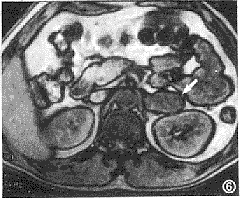

2.腫瘤定位檢查 嗜鉻細胞瘤定位檢查對手術治療必不可少。絕大部分病人通過B型超聲探測CT掃描及核磁共振成像(MRI)等非創傷性檢查可以達到準確定位。B超簡便、快速且較經濟但準確性不如後兩者CT掃描現在已比較普及對軟組織腫瘤常需做增強掃描。MRI對有些軟組織腫瘤解析度較好可以選擇採用懷疑胸腔後縱隔腫瘤時,攝胸部X線片有一定幫助懷疑膀胱嗜鉻細胞瘤者,膀胱鏡檢查和膀胱造影必不可少作者總結膀胱嗜鉻細胞瘤4例均經膀胱鏡檢查確診。腹膜後充氣造影腎上腺血管造影及靜脈腎盂造影等檢查對病人有創傷或痛苦較大又有誘發危象之危險,在B超CT和MRI越來越普及情況下,一般已無必要進行。因手術需要非做不可時在充分準備條件下選擇套用。